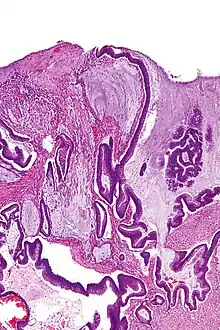

| Micrograph of a mucinous adenocarcinoma of the colon. H&E stain. | |

A mucinous neoplasm (also called colloid neoplasm) is an abnormal and excessive growth of tissue (neoplasia) with associated mucin (a fluid that sometimes resembles thyroid colloid). It arises from epithelial cells that line certain internal organs and skin, and produce mucin (the main component of mucus). A malignant mucinous neoplasm is called a mucinous carcinoma. For example, for ovarian mucinous tumors, approximately 75% are benign, 10% are borderline and 15% are malignant.